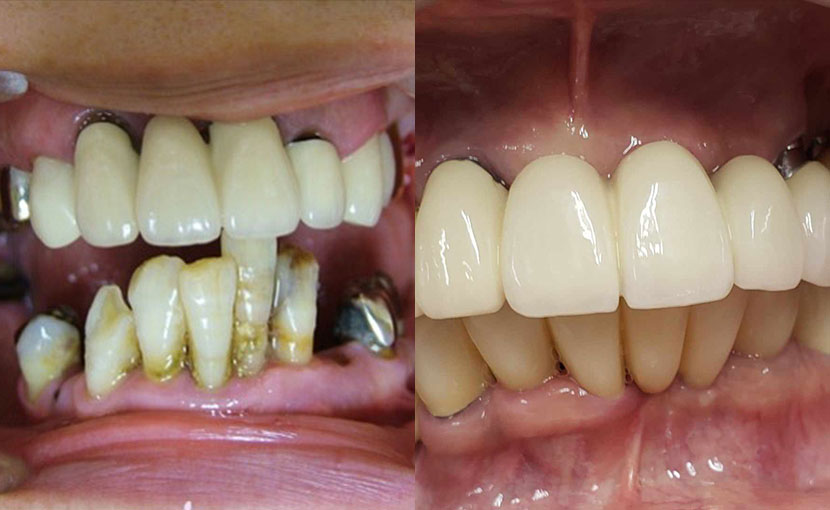

術前

• 初診:2019年、40代男性、非喫煙者、アレルギー体質(花粉症)

• 矯正診断:3級骨格性の反対咬合

• 治療方針:以前に治療したほぼ全ての歯の再治療(虫歯治療、歯内療法、歯周処置)、矯正用インプラントを用いたワイヤー矯正、修復処置(被せ物)、保定(上マウスピース、下ワイヤー)、メンテナンス